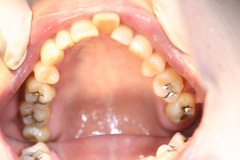

叢生の抜歯矯正の症例

Before

叢生ケースで4番の歯を4本抜歯し、唇側ブラケット矯正にて治療をした

年齢 30代

治療期間 2年6ヶ月

治療費用 1,000,000円

治療のリスク 特になし